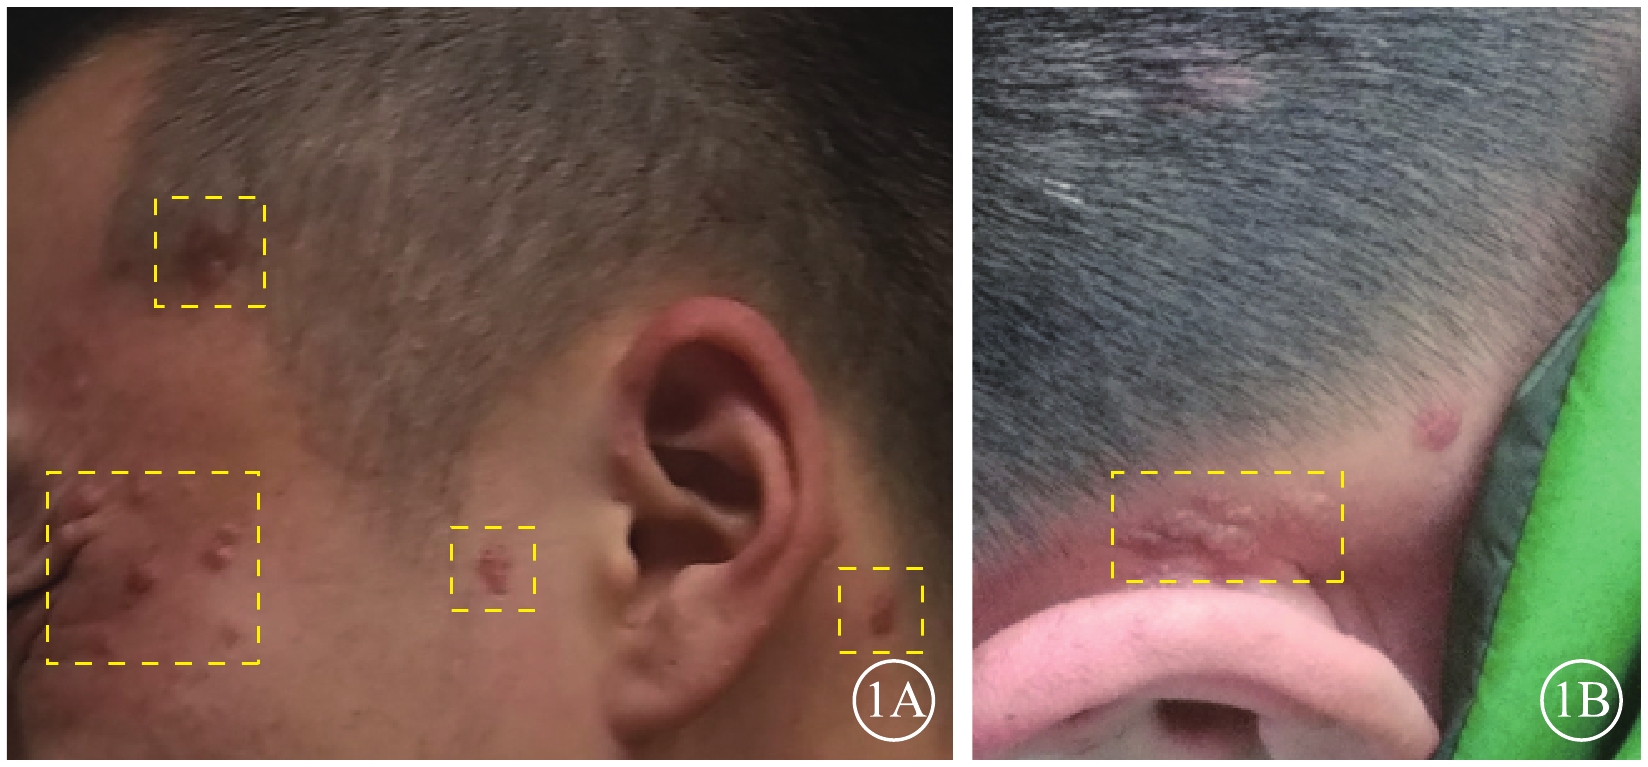

患者男,27歲。因視力下降1周來我院就診。既往有癲癇病史,目前藥物控制。右腎腫瘤切除手術后1年余,病理檢查結果提示錯構瘤。顱腦CT檢查,雙側側腦室旁、右側小腦半球多發鈣化,左側側腦室前角占位性病變。顏面部多個血管纖維瘤及耳后纖維斑塊(圖1)。雙側多根指甲根部纖維瘤。

圖1

患者皮膚病損圖。1A. 面部纖維血管瘤(黃框);1B.耳后纖維斑塊(黃框)

圖1

患者皮膚病損圖。1A. 面部纖維血管瘤(黃框);1B.耳后纖維斑塊(黃框)

患者男,27歲。因視力下降1周來我院就診。既往有癲癇病史,目前藥物控制。右腎腫瘤切除手術后1年余,病理檢查結果提示錯構瘤。顱腦CT檢查,雙側側腦室旁、右側小腦半球多發鈣化,左側側腦室前角占位性病變。顏面部多個血管纖維瘤及耳后纖維斑塊(圖1)。雙側多根指甲根部纖維瘤。

圖1

患者皮膚病損圖。1A. 面部纖維血管瘤(黃框);1B.耳后纖維斑塊(黃框)

圖1

患者皮膚病損圖。1A. 面部纖維血管瘤(黃框);1B.耳后纖維斑塊(黃框)